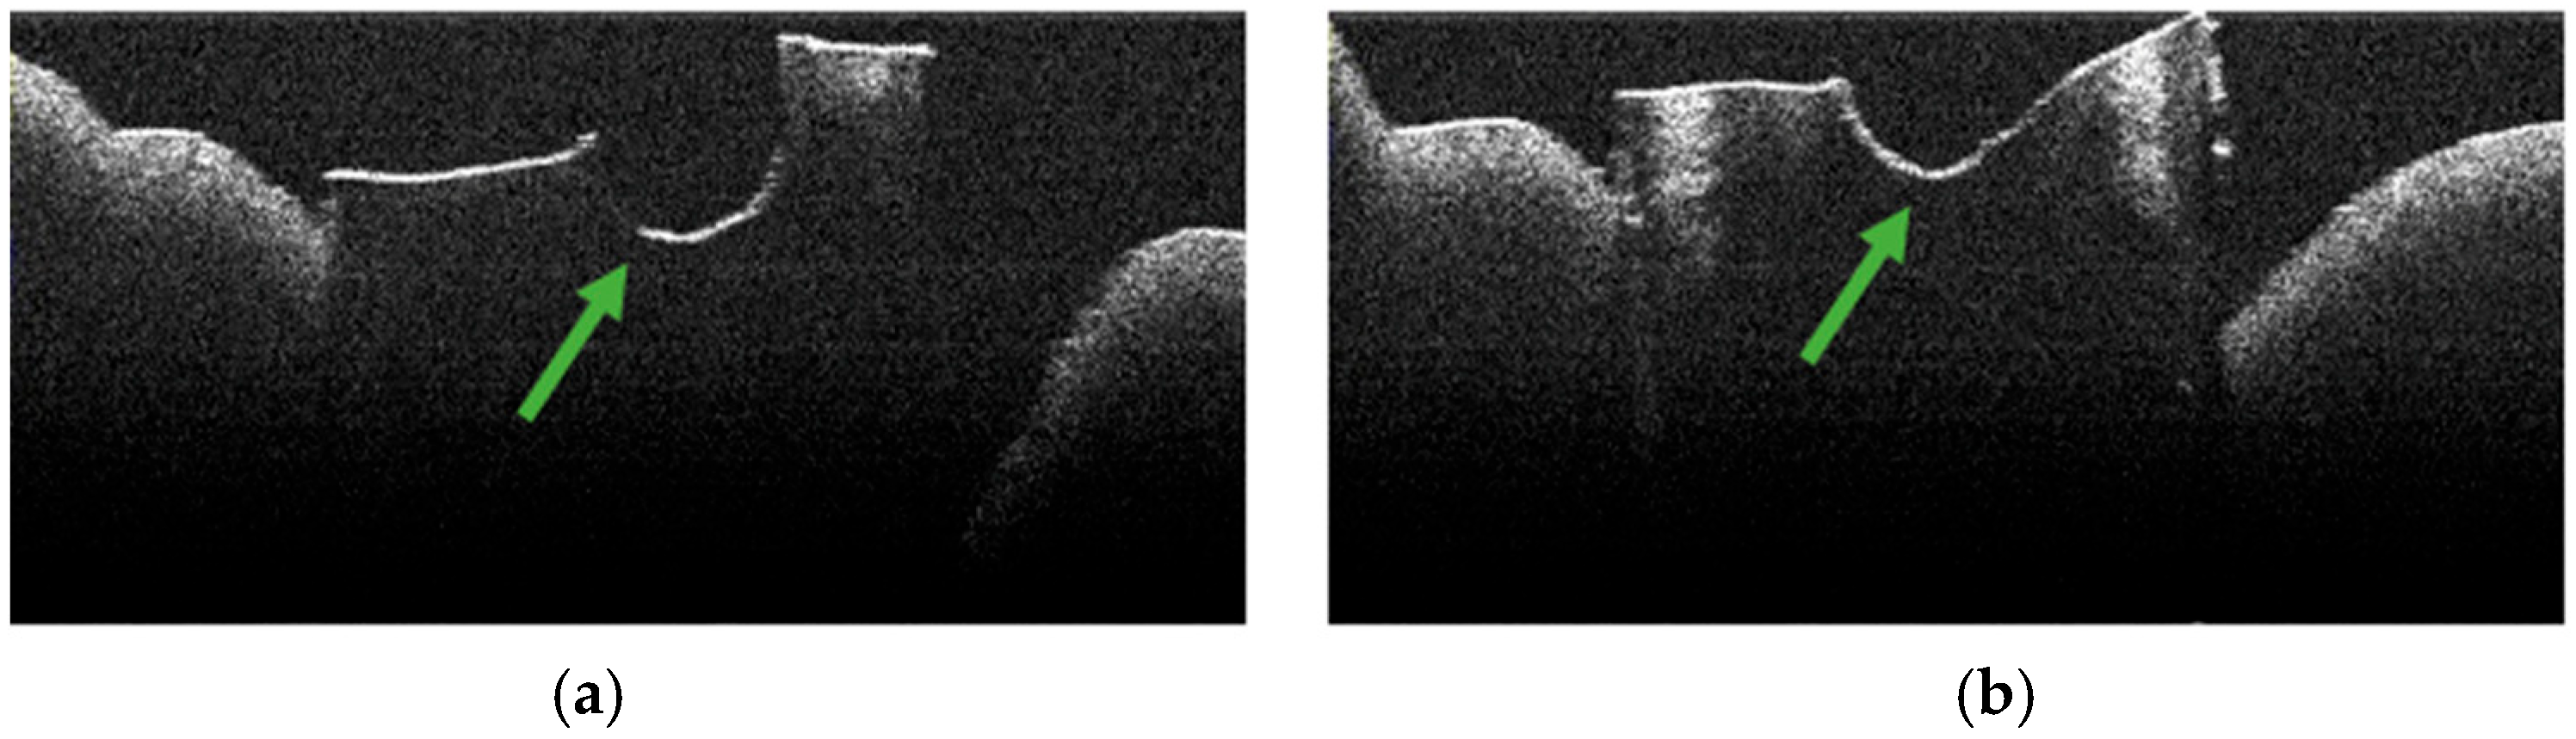

3.2. Defining OCT Signatures: Alterations vs. Artefacts

3.4. OCT Examination of Specimens from Group A